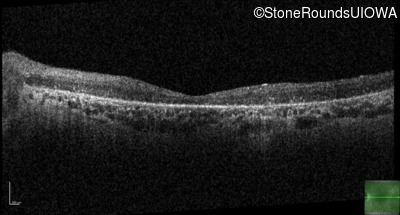

Optical Coherence Tomography - Right - 10/140 sc

Exemplar / OCT Stack